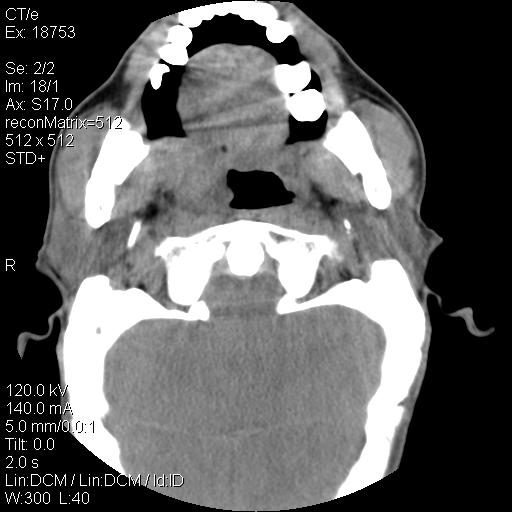

标题: CT21693:男 58岁 右侧咽部疼她2天余 PE:右侧扁桃体肿大 压痛 [打印本页]

标题: CT21693:男 58岁 右侧咽部疼她2天余 PE:右侧扁桃体肿大 压痛

右化脓性扁桃体炎症伴咽后壁脓肿形成.